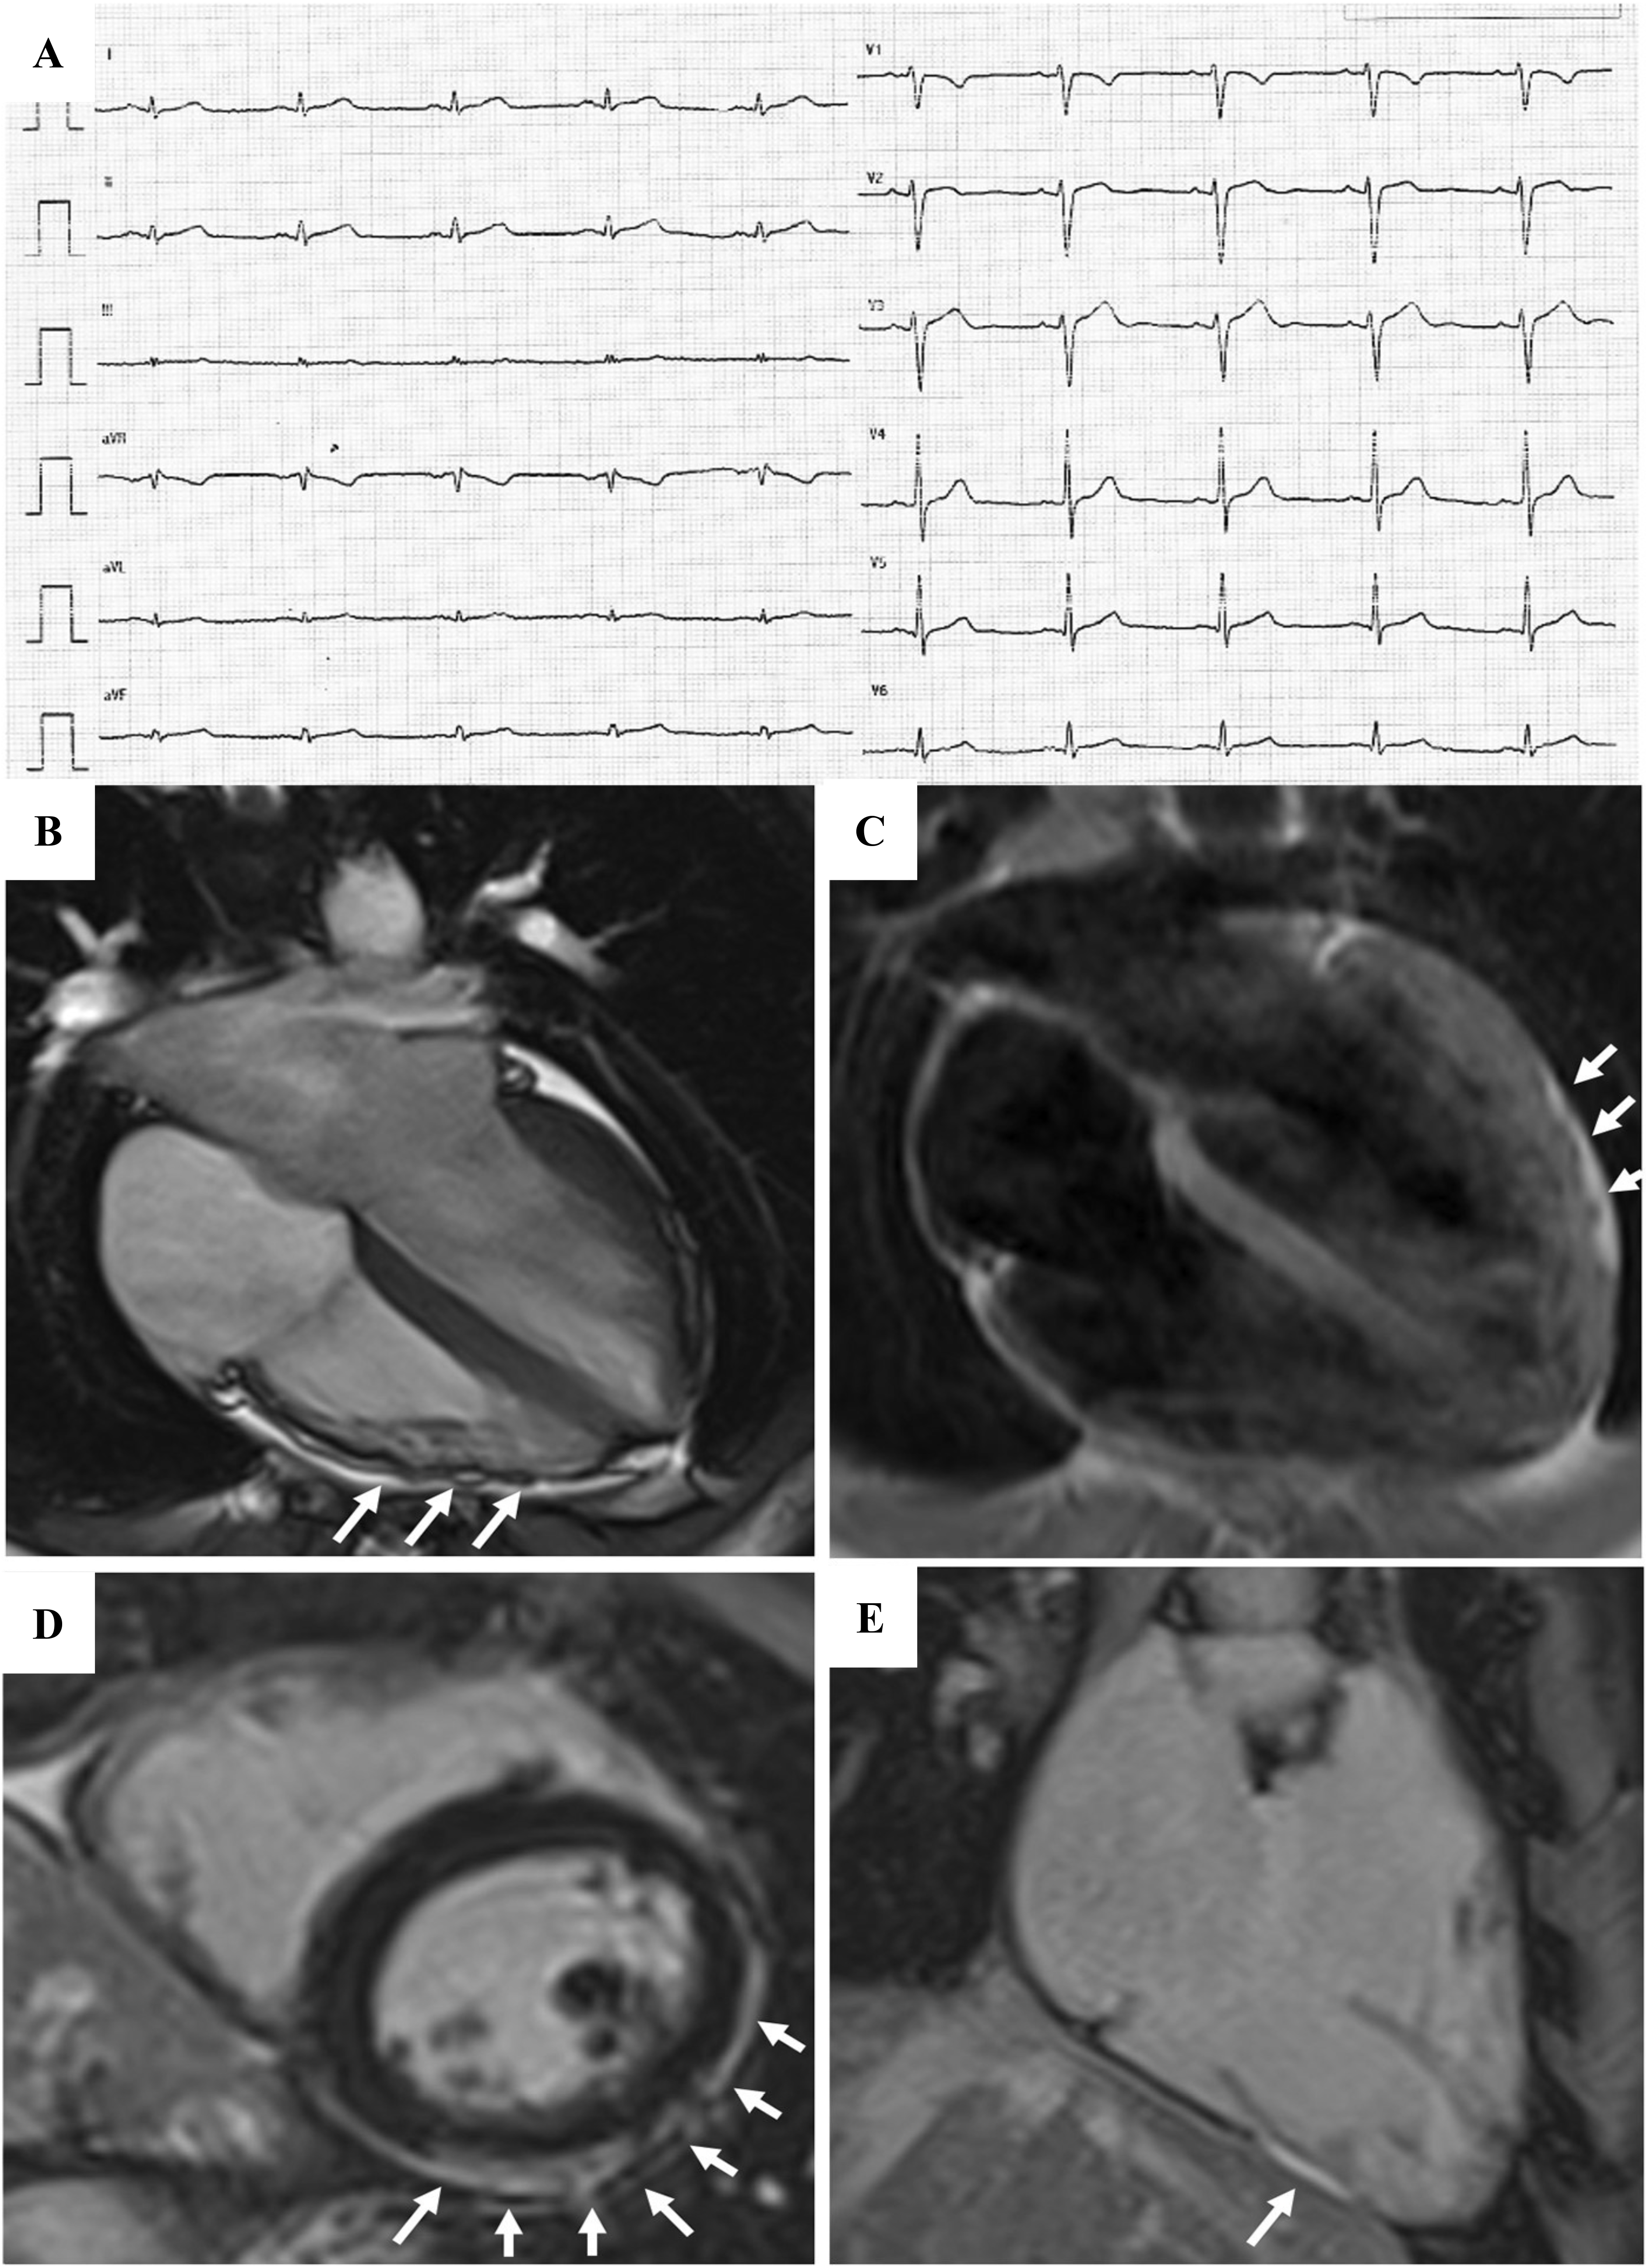

In the early stages of LV involvement, the typical non-ischemic distribution of fibro-fatty replacement sparing the subendocardial layer can explain the absence of wall motion abnormalities, dilatation, or dysfunction of the LV. Thereby, the absence of LV functional abnormalities on echo, cine-CMR or angiography cannot rule out LV involvement, and CE-CMR characterization plays a key role in detection of left-sided ACM [14, 16, 33, 34, 35, 36] (Fig. 4, Ref. [14]).

Fig. 4.Clinical and histopathological features of ALVC. Basal ECG and CMR findings in a patient who underwent cardiac transplantation because of ALVC related to a DSP gene mutation. Basal ECG revealed low QRS voltages in limb leads and flattened T-waves in infero-lateral leads (A). Post-contrast sequences on CMR (four-chamber view, B, and short-axis view, C) revealed subepicardial LGE involving the anterior septum and the whole LV free wall (“ring like” pattern) from basal to apical regions. Histology in LV inferolateral region demonstrated fibrofatty myocardial replacement in the subepicardial layer (D); a magnification of residual myocytes embedded within fibrous and fatty tissue (hematoxylin and eosin stain) (E). The diagnosis was “definite ALVC”. ALVC, arrhythmogenic left ventricular cardiomyopathy; CMR, cardiac magnetic resonance; DSP, desmoplakin gene; LGE, late gadolinium enhancement; LV, left ventricle. Adapted from Cipriani et al. [14].